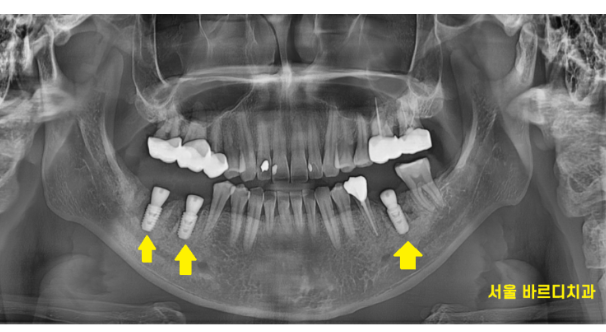

231207

환자분이 젊으신 편이라

내원 횟수를 줄여드리기로 하였습니다.

발치 당일 염증을 깨끗하게 제거하고

임플란트를 심어드렸습니다.

240402

수술 직후 사진입니다.

각도가 예술입니다.

삐뚫게 틀어지지 않고

알맞은 위치에 수술이 완료되었습니다.

240423

예전에는 금으로 치료되어있었는데요.

아래 치아이다 보니 눈에 잘 띄어

임플란트 보철은 하얀 색깔로 제작해드렸습니다.

치료 후 환자분께서

기분 나쁜 통증도 없어지고

이젠 입을 크게 벌려도 되겠다며 좋아하셨습니다.